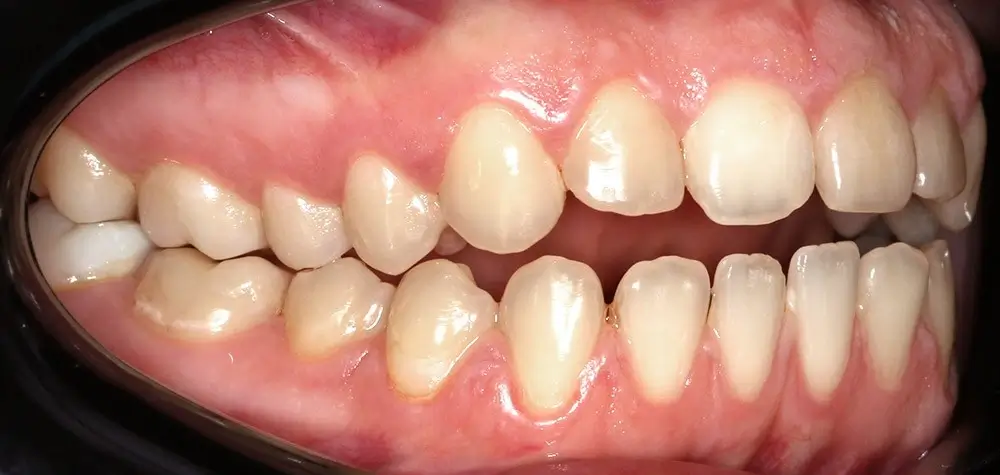

Открытый прикус - Кейс 4

Эффективность устранения дефекта прикуса посредством элайнеров FlexiLigner.

Результаты лечения